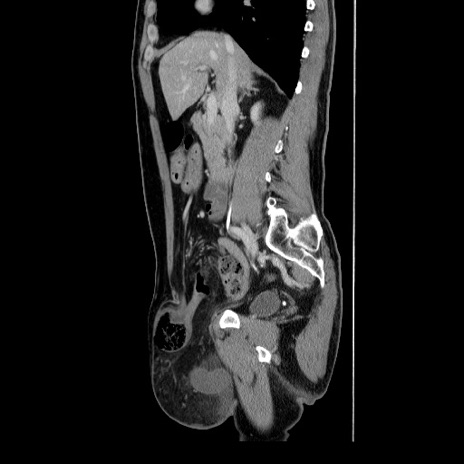

症例34(矢状断像)

【症例】60歳代 男性

【主訴】右鼠径部膨隆

【現病歴】1年程前より右鼠径部膨隆あり。自己にて還納可能だったため放置していた。3時間前より右鼠径部の脱出を認め、還納困難となり受診。

【既往歴】高血圧

【身体所見】右鼠径部に小児頭大の膨隆あり。弾性硬であり、用手還納は困難。左鼠径部にも膨隆を認める。脱出はなし。

【データ】WBC 15500、CRP 測定なし